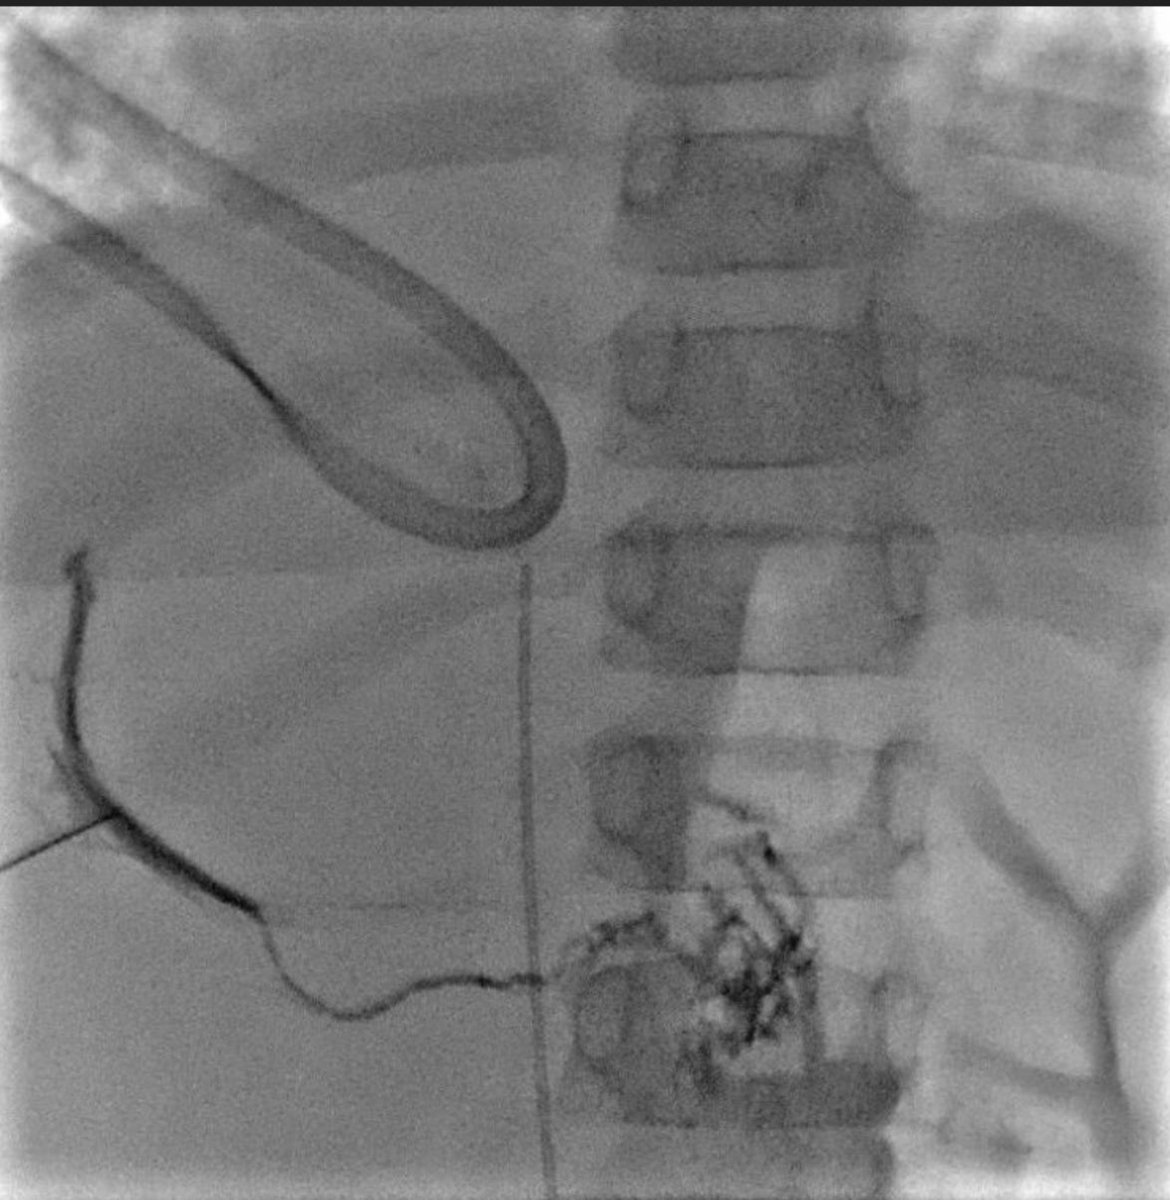

Centro interdisciplinario de anomalías vasculares CIAV del sanatorio Materdei, un orgullo formar parte de este equipo . Consultas ciavmaterdei@gmail.con #anomaliasvasculares #hemangiomas

Pediatric Interventional Radiologist. #pedsir #vascularanomalist #Anomaliasvasculares. Chief of Clinic at Garrahan Hospital and Materdei Clinic @PEDimage